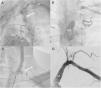

A 51-year-old man was admitted with exertional chest pain. Eleven years ago, he underwent myocardial revascularization consisting of a left internal mammary artery (LIMA) graft to the first diagonal artery. Seven years ago, he underwent carotid-subclavian bypass surgery due to subclavian artery stenosis. After the second surgery, he was stable, but he developed exertional chest pain last year. His physical examination was remarkable for the presence of weak left radial and brachial pulses, with a significant difference in blood pressure between the right (130/85 mmHg) and left (90/60 mmHg) arms. Electrocardiogram showed normal sinus rhythm without ischemic changes. Contrast injection into the left main coronary artery showed chronic total occlusion of the circumflex artery and demonstrated a striking retrograde flow from the coronary tree through the graft (Figure A; Video 1). A left subclavian artery angiography revealed total occlusion proximal to the origin of the LIMA (Figure B; Video 2). A left common carotid artery angiography showed the total occlusion of the carotid-subclavian bypass graft (Figure C; Video 3). We decided on percutaneous intervention of the left subclavian artery, and the patient was successfully treated with subclavian balloon angioplasty and stent placement (Figure D; Video 4-8).

A. Left coronary angiography showing retrograde flow from the coronary tree through the mammary artery bypass graft (arrow). B. Left subclavian angiography revealed total occlusion proximal to the left internal mammary artery graft to the first diagonal artery. C. Left common carotid angiography demonstrated the total occlusion of the carotid-subclavian bypass graft (arrow). D. Digital subtraction angiography of the left subclavian artery after stent placement showed successful treatment of the subclavian occlusion.

D1: first diagonal artery; LAD: left anterior descending artery; LCCA: left common carotid artery; SA: subclavian artery.